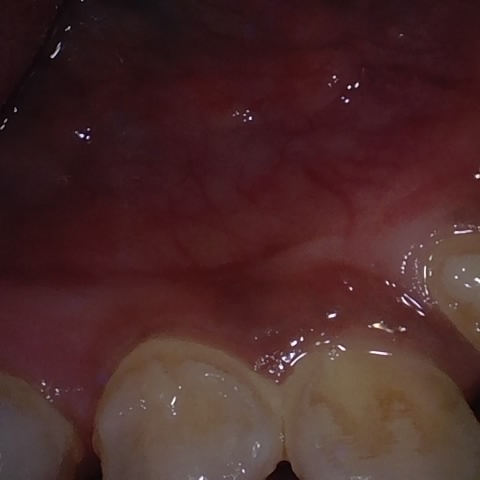

Annotated as "Good"